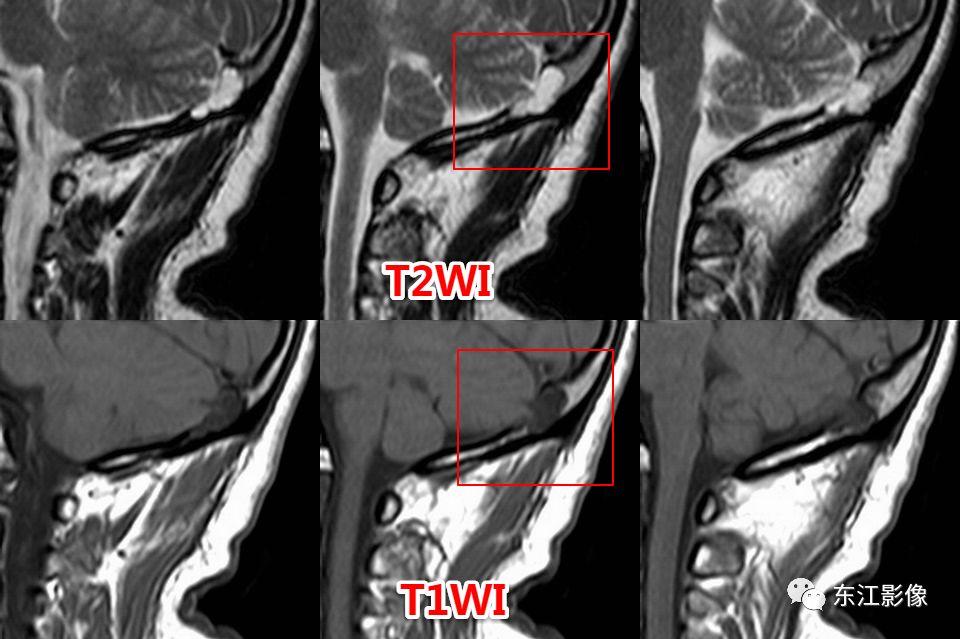

5. 脑脊液流动伪影

- 脑脊液流动伪影主要见于T2WI、FLAIR,主要是长TE序列容易出现流空效应的缘故。

- 但由于脑脊液流动方向、速率不一等因素的影响,呈现为非脑脊液信号影像,部分呈囊样。

- 常见于第三脑室、侧脑室室间孔旁区、脑干周围脑池(这些区域结构复杂)。

- 鉴别要点,T1WI、增强未能辨认;DWI与邻近一致的无信号;无占位效应。

桥前池脑脊液流动伪影。